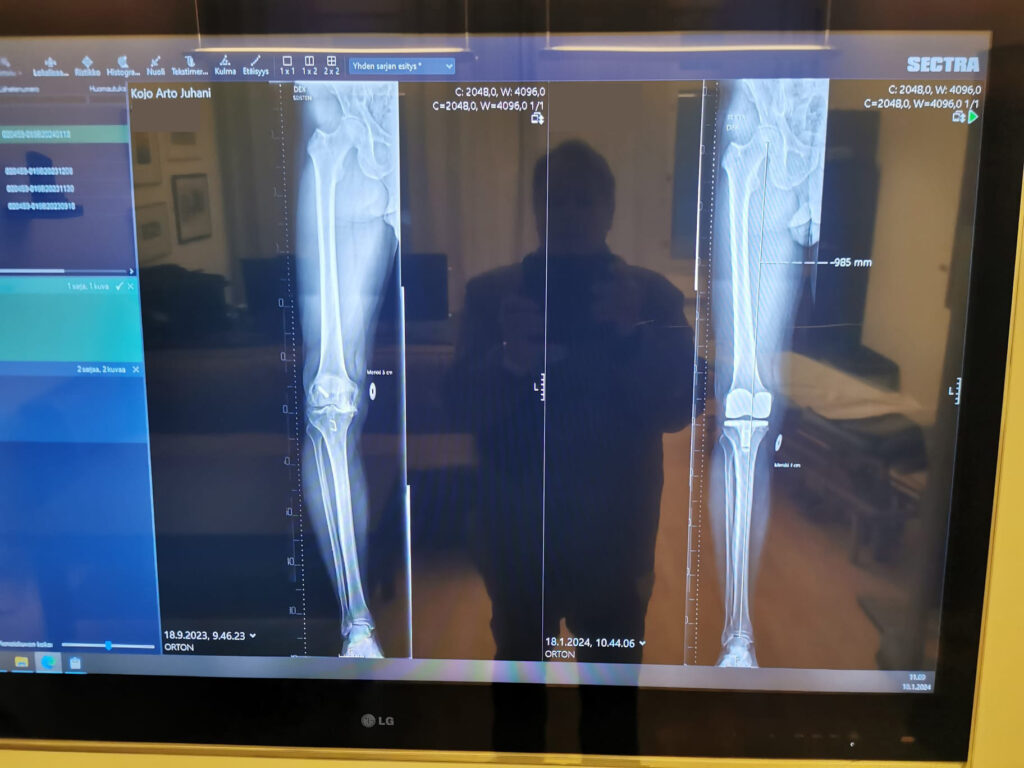

Liikkumisen lisääntyessä havaitsin myös, että leikattu alaraaja, joka oli ennen leikkausta hieman toista lyhyempi, oli nyt palautunut entiseen mittaansa. Pituuseron tasoittumisen takia jouduin jonkin aikaa kiinnittämään askellukseeni tarkempaa huomiota. Oletan, että muutoksen seurauksena leikatun jalan reiden ulko-osa oli sekin jonkin aikaa hyvin arka kosketukselle. Pariin viikkoon en pystynyt nukkumaan oikealla kyljellä ja reiden etu- ja sivuosaa piti hieroa päivittäin faskiatyyppisellä käsittelyllä. Onneksi se poisti kivun aina hetkeksi.

Viikolla 6 vuorossa oli jälkitarkistus ja tapaaminen Ortonissa, jossa käytiin läpi vielä aikaisempaa tarkemmin leikkaus ja sen kriittiset vaiheet. Pääsin myös samalla esittämään monia ortopedisiä kysymyksiä, jotka olivat mieltäni askarruttaneet. Polveni oli ollut normaalia haastavampi leikattava aikaisemman polvivammani vuoksi.

Polvi oli odotettua isompi työmaa kirurgille

Palaan vielä hetkeksi omaan tapaukseeni, koska lähtökohtani leikkaukseen ei ollut se perinteinen. Seuraava teksti on tarkoitettu ensi sijaisesti fysioterapeuteille ja muille alan ammattilaisille, mutta toki muutkin saavat siitä taustatietoa.

Kun sain leikkauskertomuksen luettavakseni sairaalassa, minun piti lukea se muutamaan kertaan läpi ennenkuin ymmärsin, että kaikki ei mennytkään niin kuin normaalissa leikkauksessa, jossa potilaalla ei ole aikaisempaa vammahistoriaa. Sen kyllä tiesin, että polven alueella on arpikudosta, mutta lähtötilanteenki oli paljon huonompi kuin odotin.